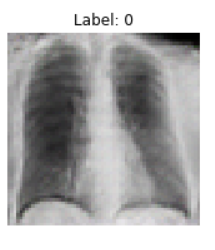

With an x-ray image of an individual's healthy lungs, we are able to use machine learning techniques to add features indicative of COVID-19. Given that we're handling an image, we took an approach that applied the use of Generative Adversarial Networks (GANs) to create a new image of the same lungs except with added COVID-19 properties. COVID-19 may manifest in an x-ray as cloudy regions in the lungs, known as ground glass opacities.

We built an Auxiliary-Classifier GAN (arXiv:1610.09585) that produces lung x-rays with or without COVID-19 properties based on an inputted condition. After the generator has been trained, an inputted healthy lung x-ray is encoded into a latent vector via gradient descent with a VGG perceptual loss (arXiv:1802.05701, arXiv:1603.08155). Then, a condition vector is concatenated with this latent vector and run through the generator to produce the same lung x-ray but with COVID-19 ground glass opacities. This model was written in Pytorch. Hyperparameters and code can be found at the following GitHub. The training data included around 2000 total 64x64 COVID positive and negative x-rays.